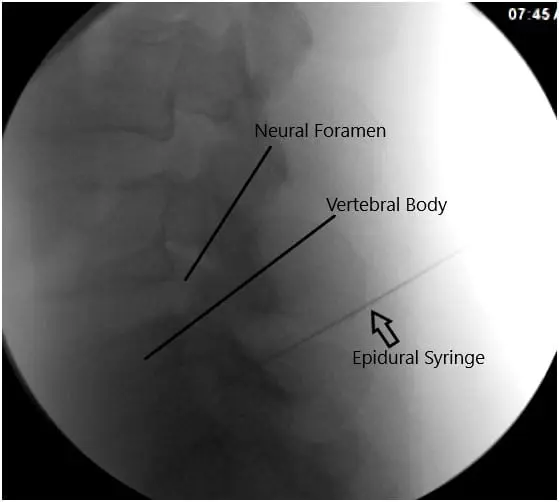

After aseptic prep and drape under C-arm, the needle was introduced to reach the level of the L5-S1 foramen. It was checked under C-arm and found to be in the satisfactory position in AP and lateral view; 0.5 cc of iodine dye was introduced and found to form a good nervogram; 40 mg of Kenalog mixed with 1 cc of 0.5% Marcaine was introduced into the L5 nerve root sheath on the right side.

Intraoperative Fluoroscopy Images.